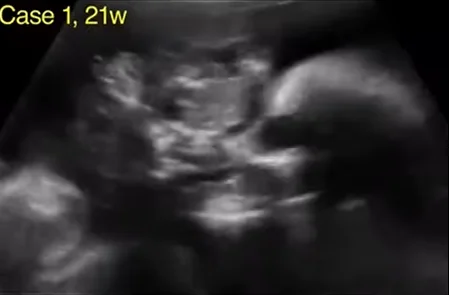

U quái vùng hầu họng thai (Epignathus)